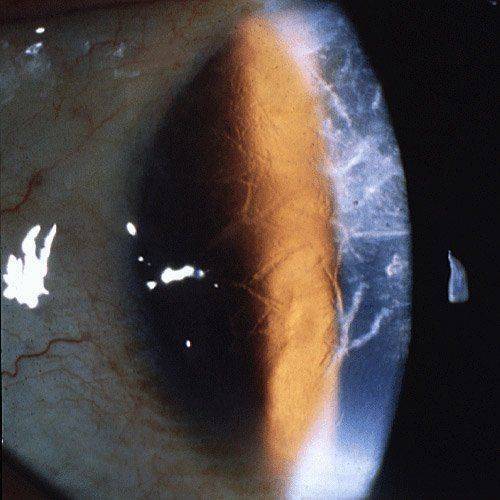

Кератоконус

Кератоконусом называется малоизученная патология роговицы, называемая также пеллюцидная маргинальная дегенерация. Симптомы, отмечающиеся при этой разновидности характерны для всех видов дегенерации. Характеризуется патология истончением и деформацией роговой оболочки в форме конуса. Лечение в таких случаях осуществляется комплексное с применением медикаментов для облегчения симптоматики, физиотерапевтических процедур. Также может быть показано хирургическое вмешательство.